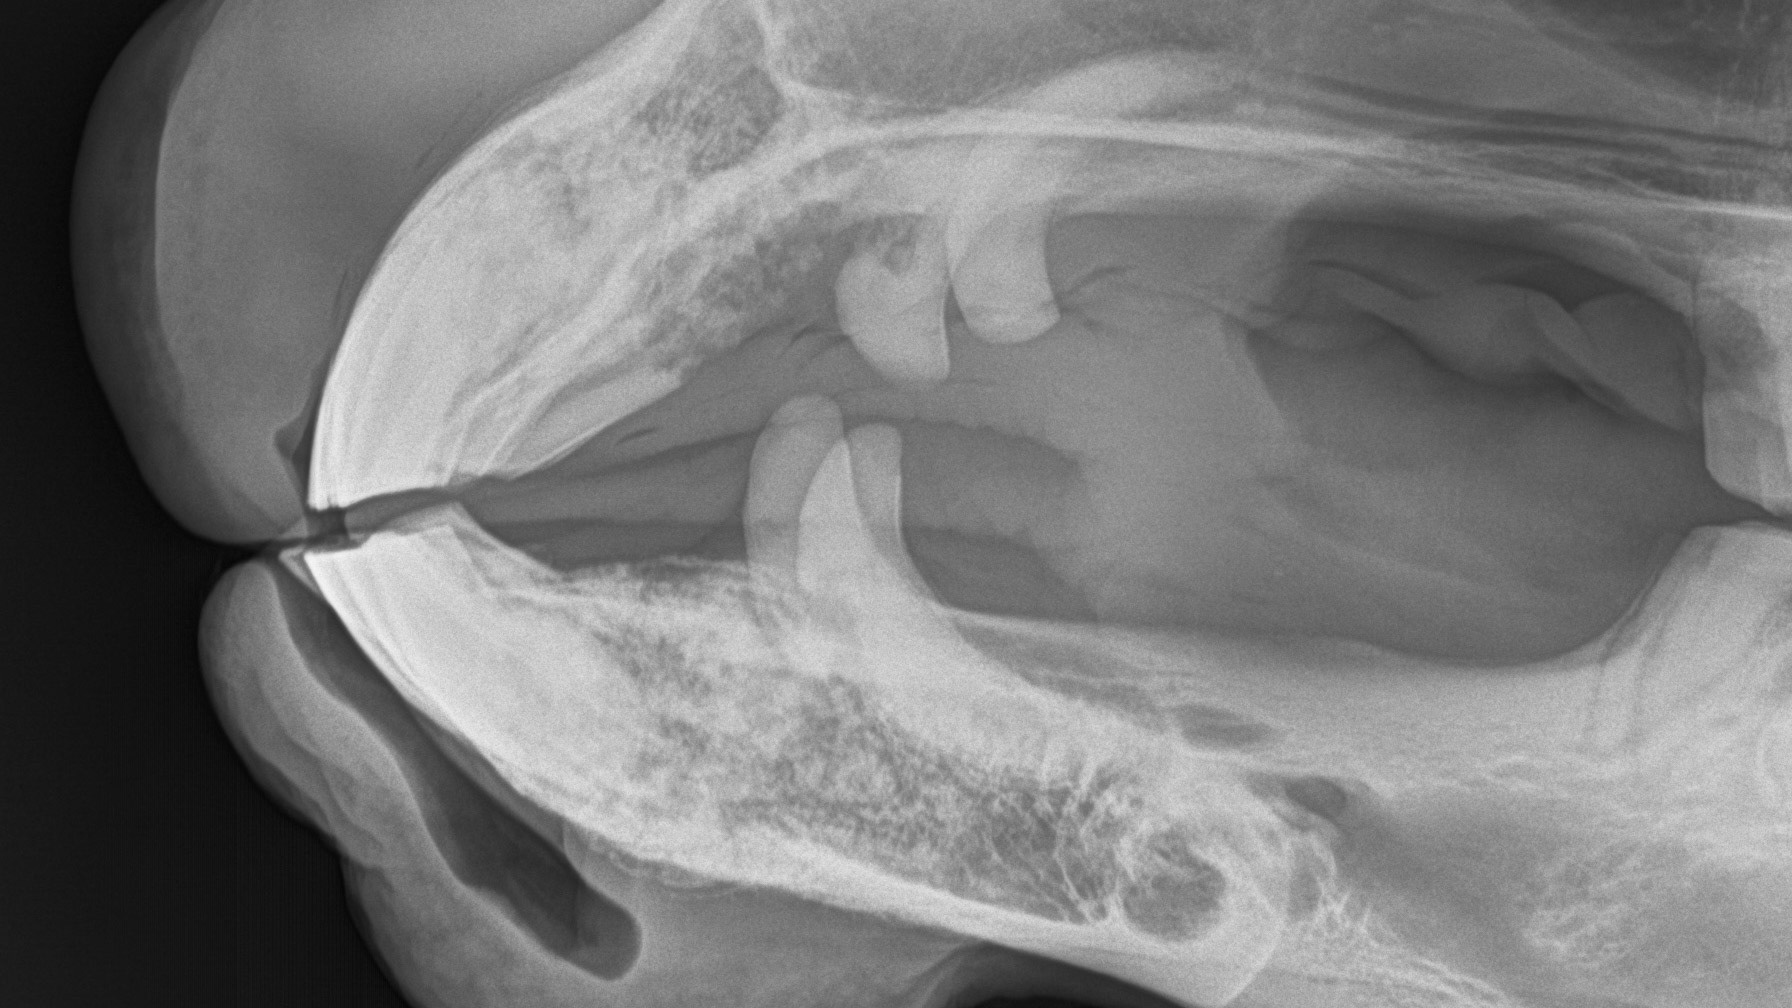

A radiograph (X-ray) of the canines and incisor teeth in a horse with EOTRH. Note the lacy look of the bone where the teeth insert as well as the enlargement of the tooth roots as they struggle to hang on.